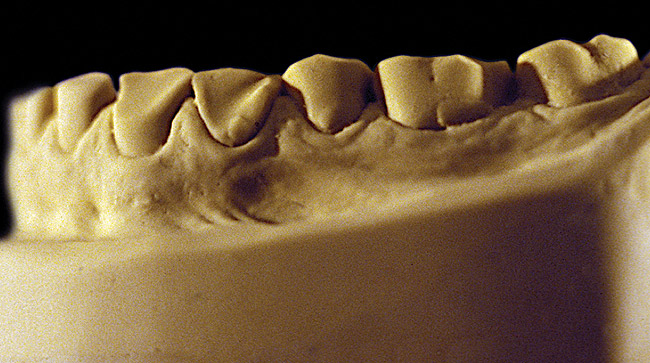

Figure 6  Moderate NCLTS from bruxism, mandibular arch.

Figure 6

The patient shown in Figure 3 and Figure 4 exhibited severe NCLTS from bruxism. Examination of the casts indicated that the NCLTS was progressively greater toward the anterior teeth. Cupping and cratering was not present because there was no secondary cause. Figure 5 and Figure 6 detail another bruxism patient, but to a lesser degree and one with cupping/cratering caused by toothpaste. The cups or craters were not caused from bruxism because the teeth could not touch the bottom of the invaginations. In both featured patients, upon hand-articulating the casts, the NCLTS facets matched up and the diagnosis of bruxism was confirmed.